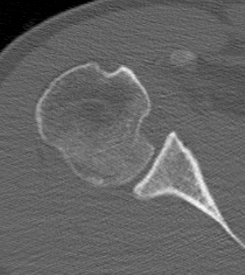

CT scan

Confirms dislocation

Reverse Hill Sachs

Humeral head defect

- caused by impaction of anterior humeral head on posterior glenoid

- intra-articular

- measured as a percentage of the articular surface

Lesser tuberosity fractures

Posterior glenoid fractures / bony bankart